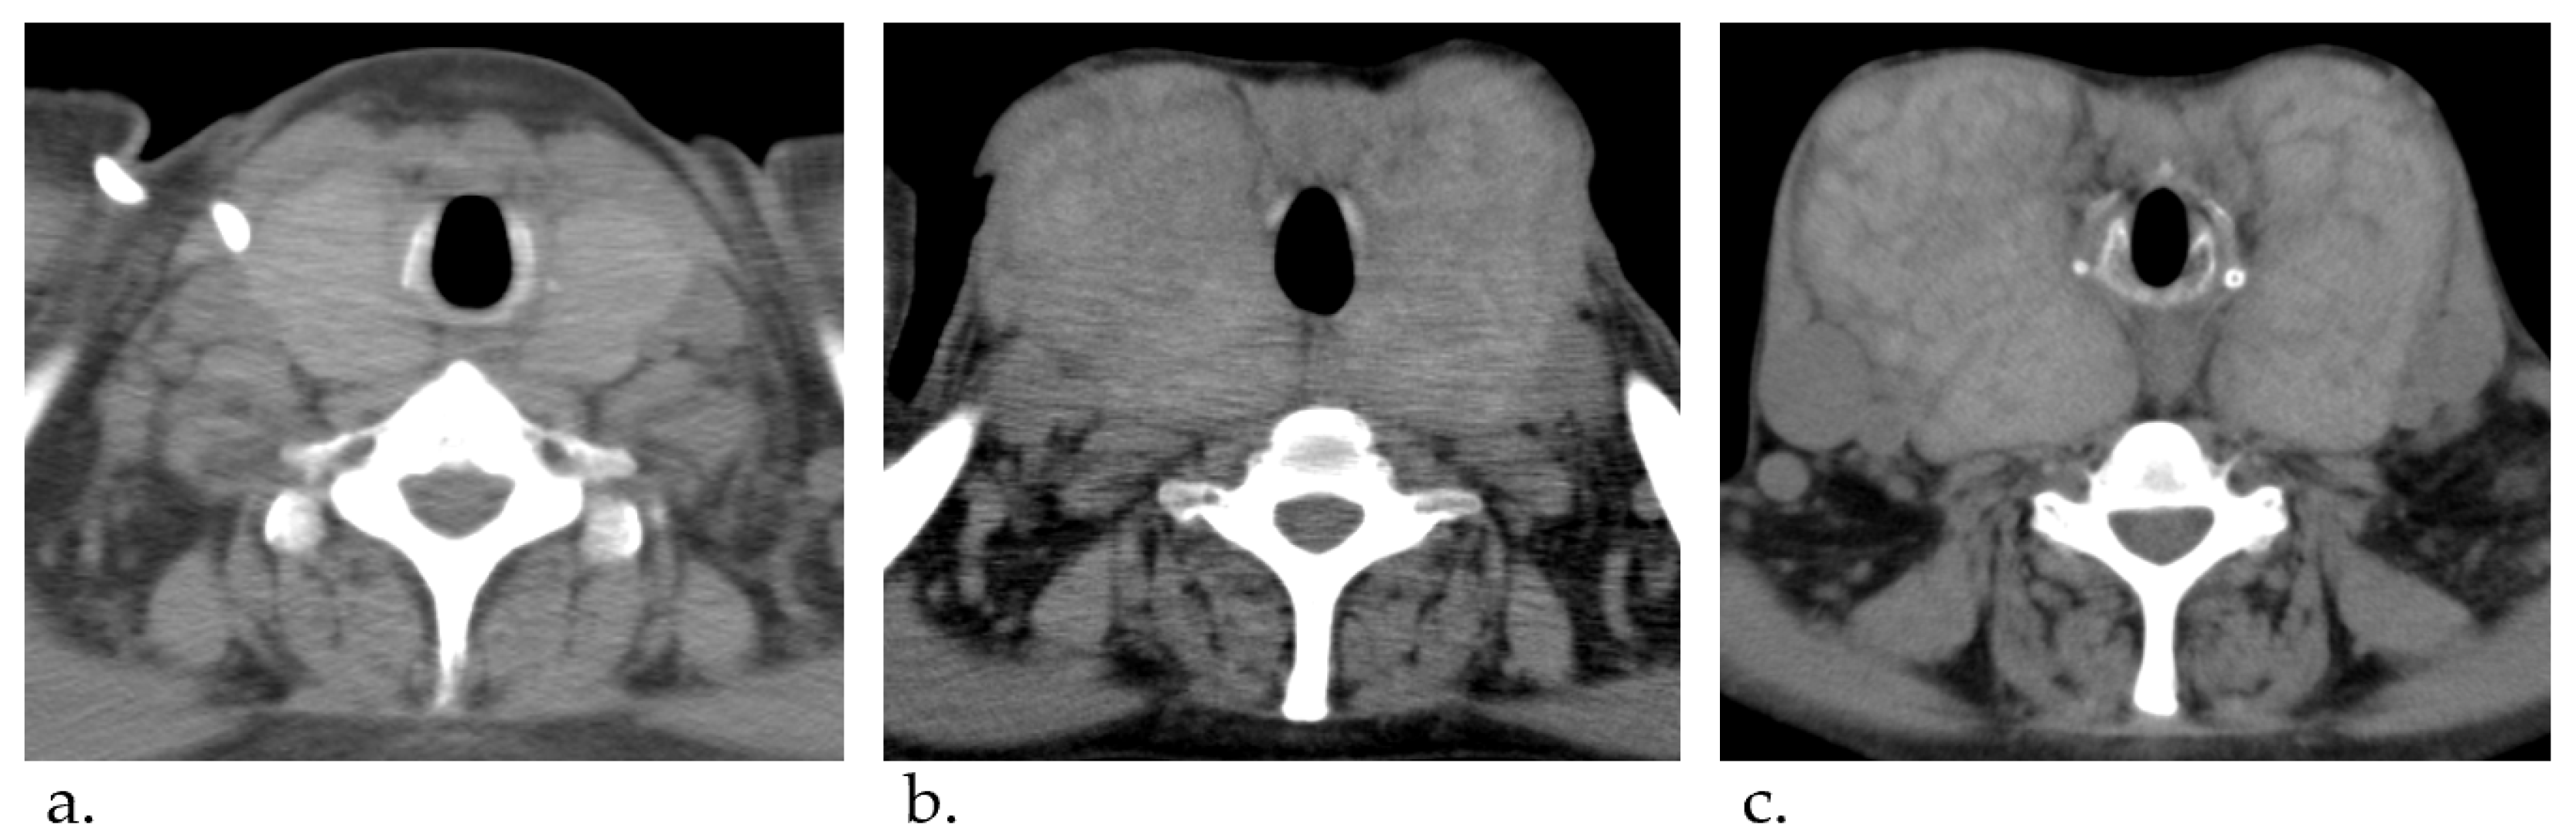

At the age of 45, the dose of epoprostenol was increased to 32.5 ng/kg/min, but the mean pulmonary artery pressure on the right heart catheter was high at 58 mmHg, which was not enough controlled. At that time, the enlargement of her thyroid gland was mild (Figure 1a). Therefore, we further titrated the dose of epoprostenol. After 16 years of treatment, epoprostenol was maintained at 60–70 ng/kg/min and we could reduce it to around 30 mmHg. Although the patient’s thyroid function was controlled by therapy for Graves’ disease using thiamazole and levothyroxine, the enlargement of her thyroid gland gradually worsened (Figure 1b). At the age of 54, thyroid studies showed TSH = 3.33 μIU/mL, free T3 = 1.18 pg/mL, and free T4 = 3.06 pg/mL. Nevertheless, her goiter further worsened as epoprostenol was titrated (Figure 1c).

Figure 1.

Computed tomography imaging course of thyroid gland enlargement. (a) At 45 years of age. (b) At 52 years of age. (c) At 54 years of age. The thyroid gland gradually was enlarged.